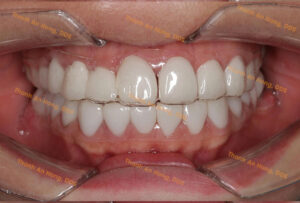

HÌNH ẢNH THỰC TẾ

Khay trong suốt chỉnh lệch đường giữa với toàn hàm là răng sứ